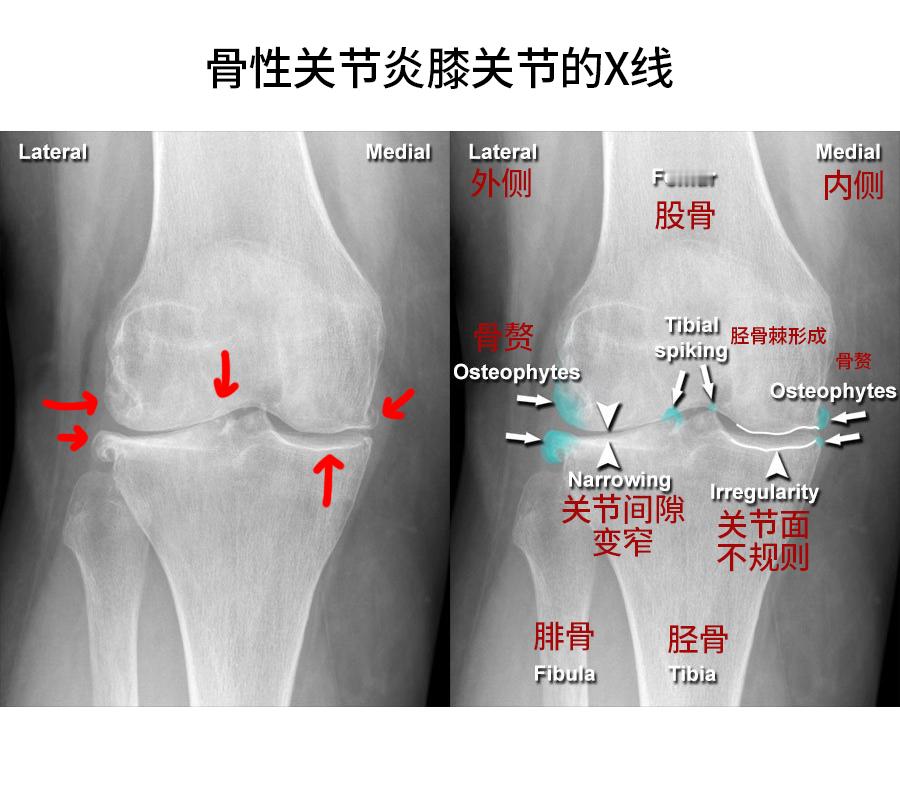

来看【正常】膝关节和【骨性关节炎】膝关节的片子——尤其是软骨,正常的膝关节,那条

来看【正常】膝关节和【骨性关节炎】膝关节的片子——尤其是软骨,正常的膝关节,那条线/面是很平滑的,但关节炎的那张,就是曲曲折折不规则的